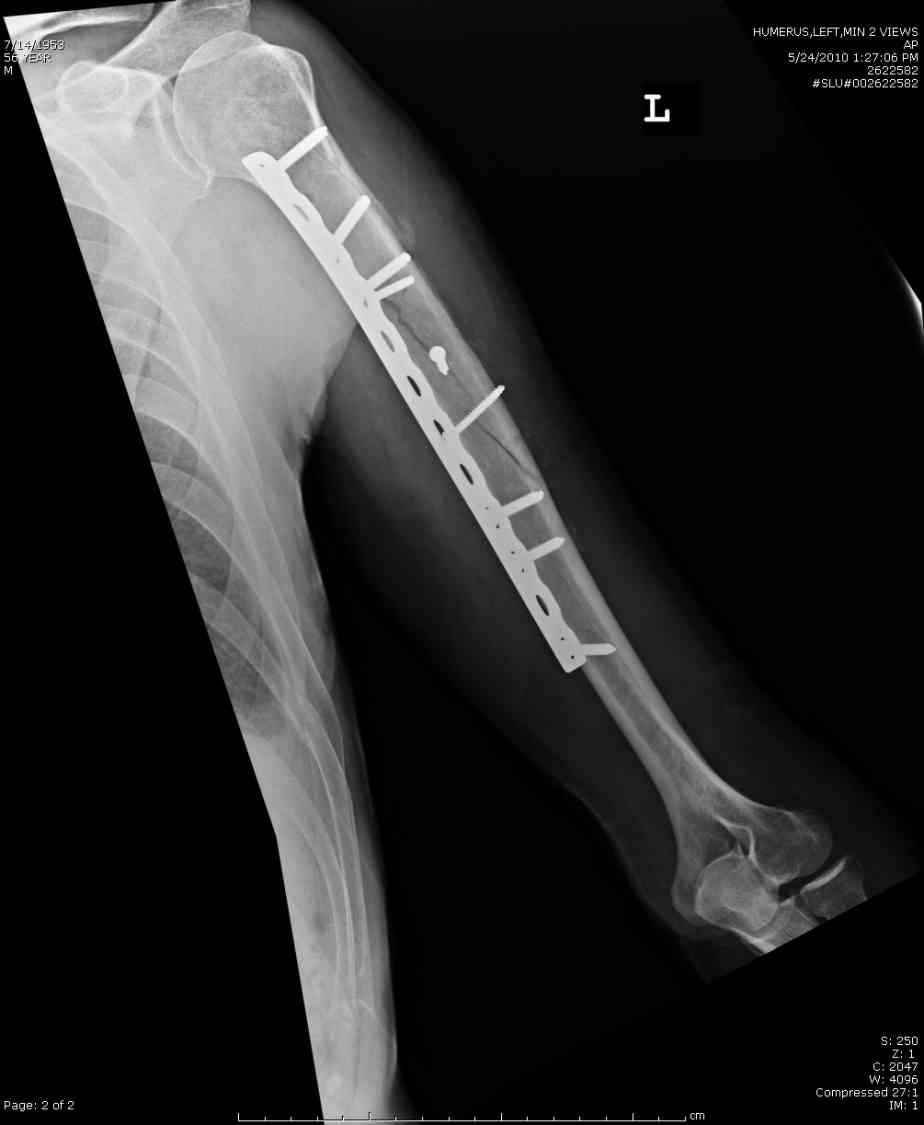

Александр А. 01 Июль 2010, 00:29

Добрый вечер!

Приложение как пример.

Что иллюстрирует этот пример? Это была множественная травма? Если это был изолированный перелом, то "золотой стандарт" - консервативное лечение.

Консервативно он уже лечился до этой операции в течение трёх с половиной месяцев.

А именно такой вариант операции выбран из экономических соображений.

вообще, торчашие в субакромиальное пространство шипы оставляют неизгладимое впечатление. Не думаю, что таким имплантом есть смысл гордиться

Снимок с имплантом из металла с памятью формы получился "sexy", но нарушены все каноны остеосинтеза. Потому что при комбинации двух ущербных систем одновременно повреждается внутри канальное и наружное кровообращение.

Кроме интрамедуллярного остеосинтеза, имеются другие варианты фиксации, наружный фиксатор и например здесь перелом плеча с повреждением нерва леченный открытым методом. Применен задний доступ с инспекцией нерва, межфрагментарная компрессия, фиксация узкой пластиной 4.5 мм.